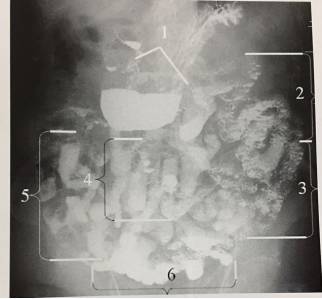

11、小肠Cole分组

1、第一组,十二指肠;2、第二组,上部空肠,范围自十二指肠空肠曲自左至胃大弯的下方或后方的左上腹小肠。3、第三组,下部空肠,位于左侧髂窝的小肠,在第二组的下面,二者无明显界线。4、第四组,上部回肠,由3-4个垂直的肠曲所组成,位于腹部中央,稍偏脐部右下方。5、第五组,中部回肠,位于右腹部,见于升结肠右方,其方向与第四组相似,多为垂直的肠曲。6、第六组,下部回肠,位于盆腔,长在正中线右方,其方向不变。